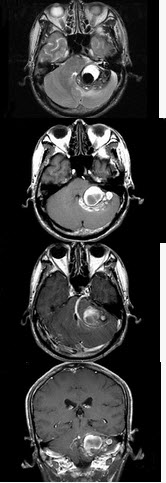

男,45岁,反复呕吐近1个月,加重5天,根据所提供图像,最可能的诊断是()

A . 海绵状血管瘤

B . 静脉血管畸形

C . 脑出血

D . 动静脉畸形

E . 小脑胶质瘤并出血

[单选题]男,45岁,反复呕吐近1个月,加重5天,根据所提供图像,最可能的诊断是()A.海绵状血管瘤B.静脉血管畸形C.脑出血D.动静脉畸形E.小脑胶质瘤并出血